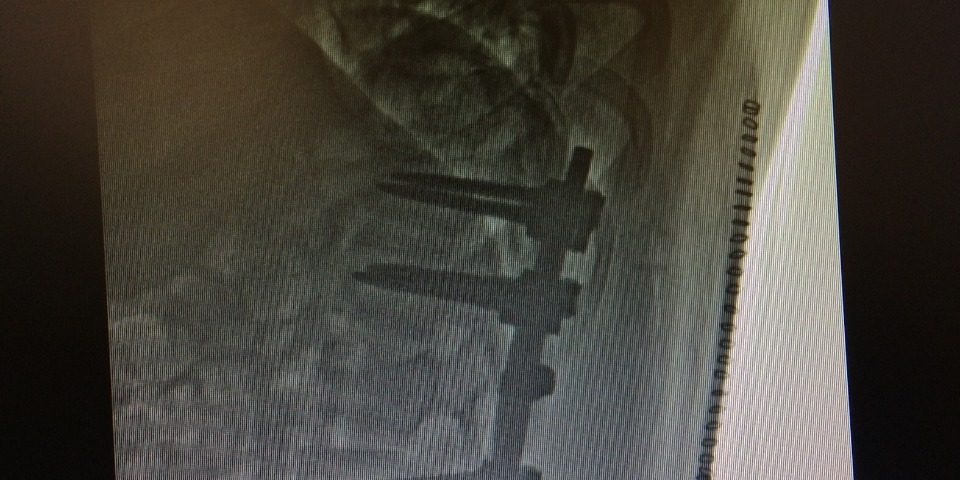

Lumbar Spine Fixation

Lumbar Spine Fracture before Surgery

Before Surgery CT of Quadriplegic Patient